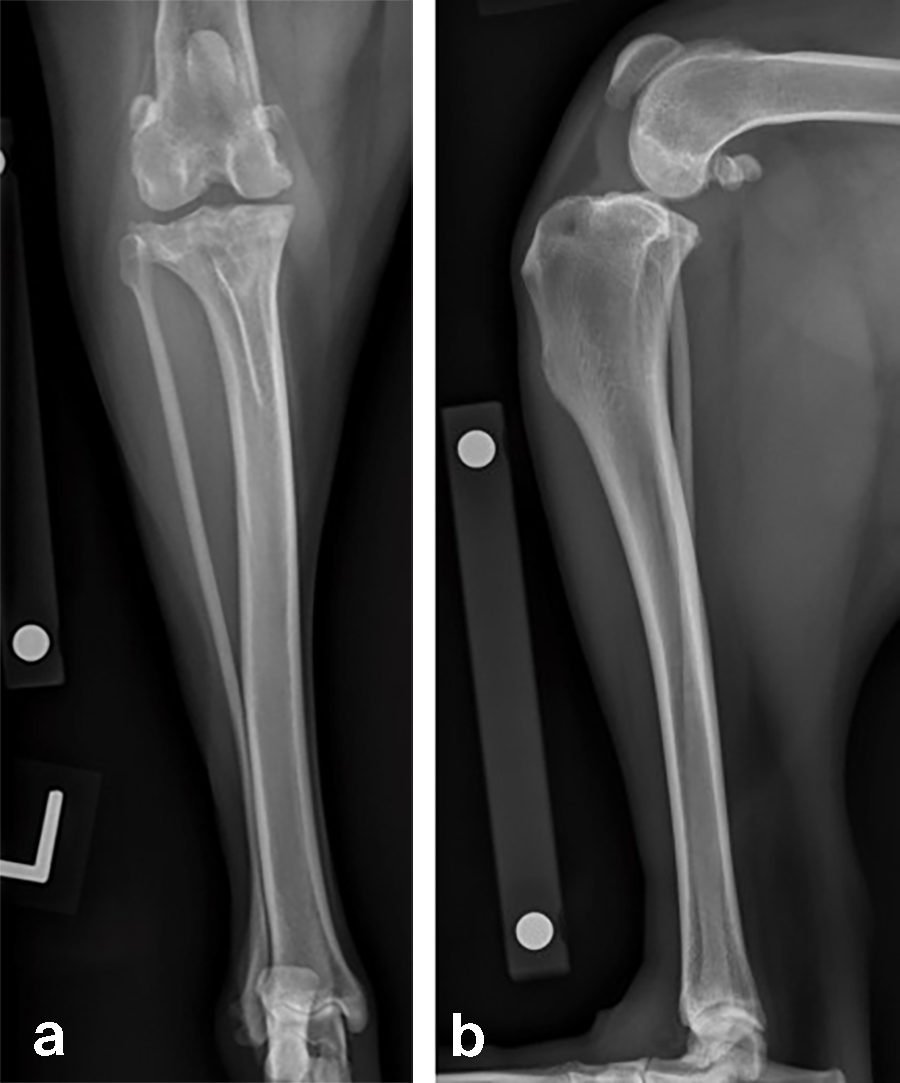

A 32 kg male neutered Golden Retriever presented with a recent deterioration of chronic right hind limb lameness. Physical examination revealed a cranial cruciate ligament rupture.

Follow-up x-rays at 8 weeks postoperatively revealed stable implants, stable bone segments, and healing of the osteotomy. The clinical outcome was satisfactory.